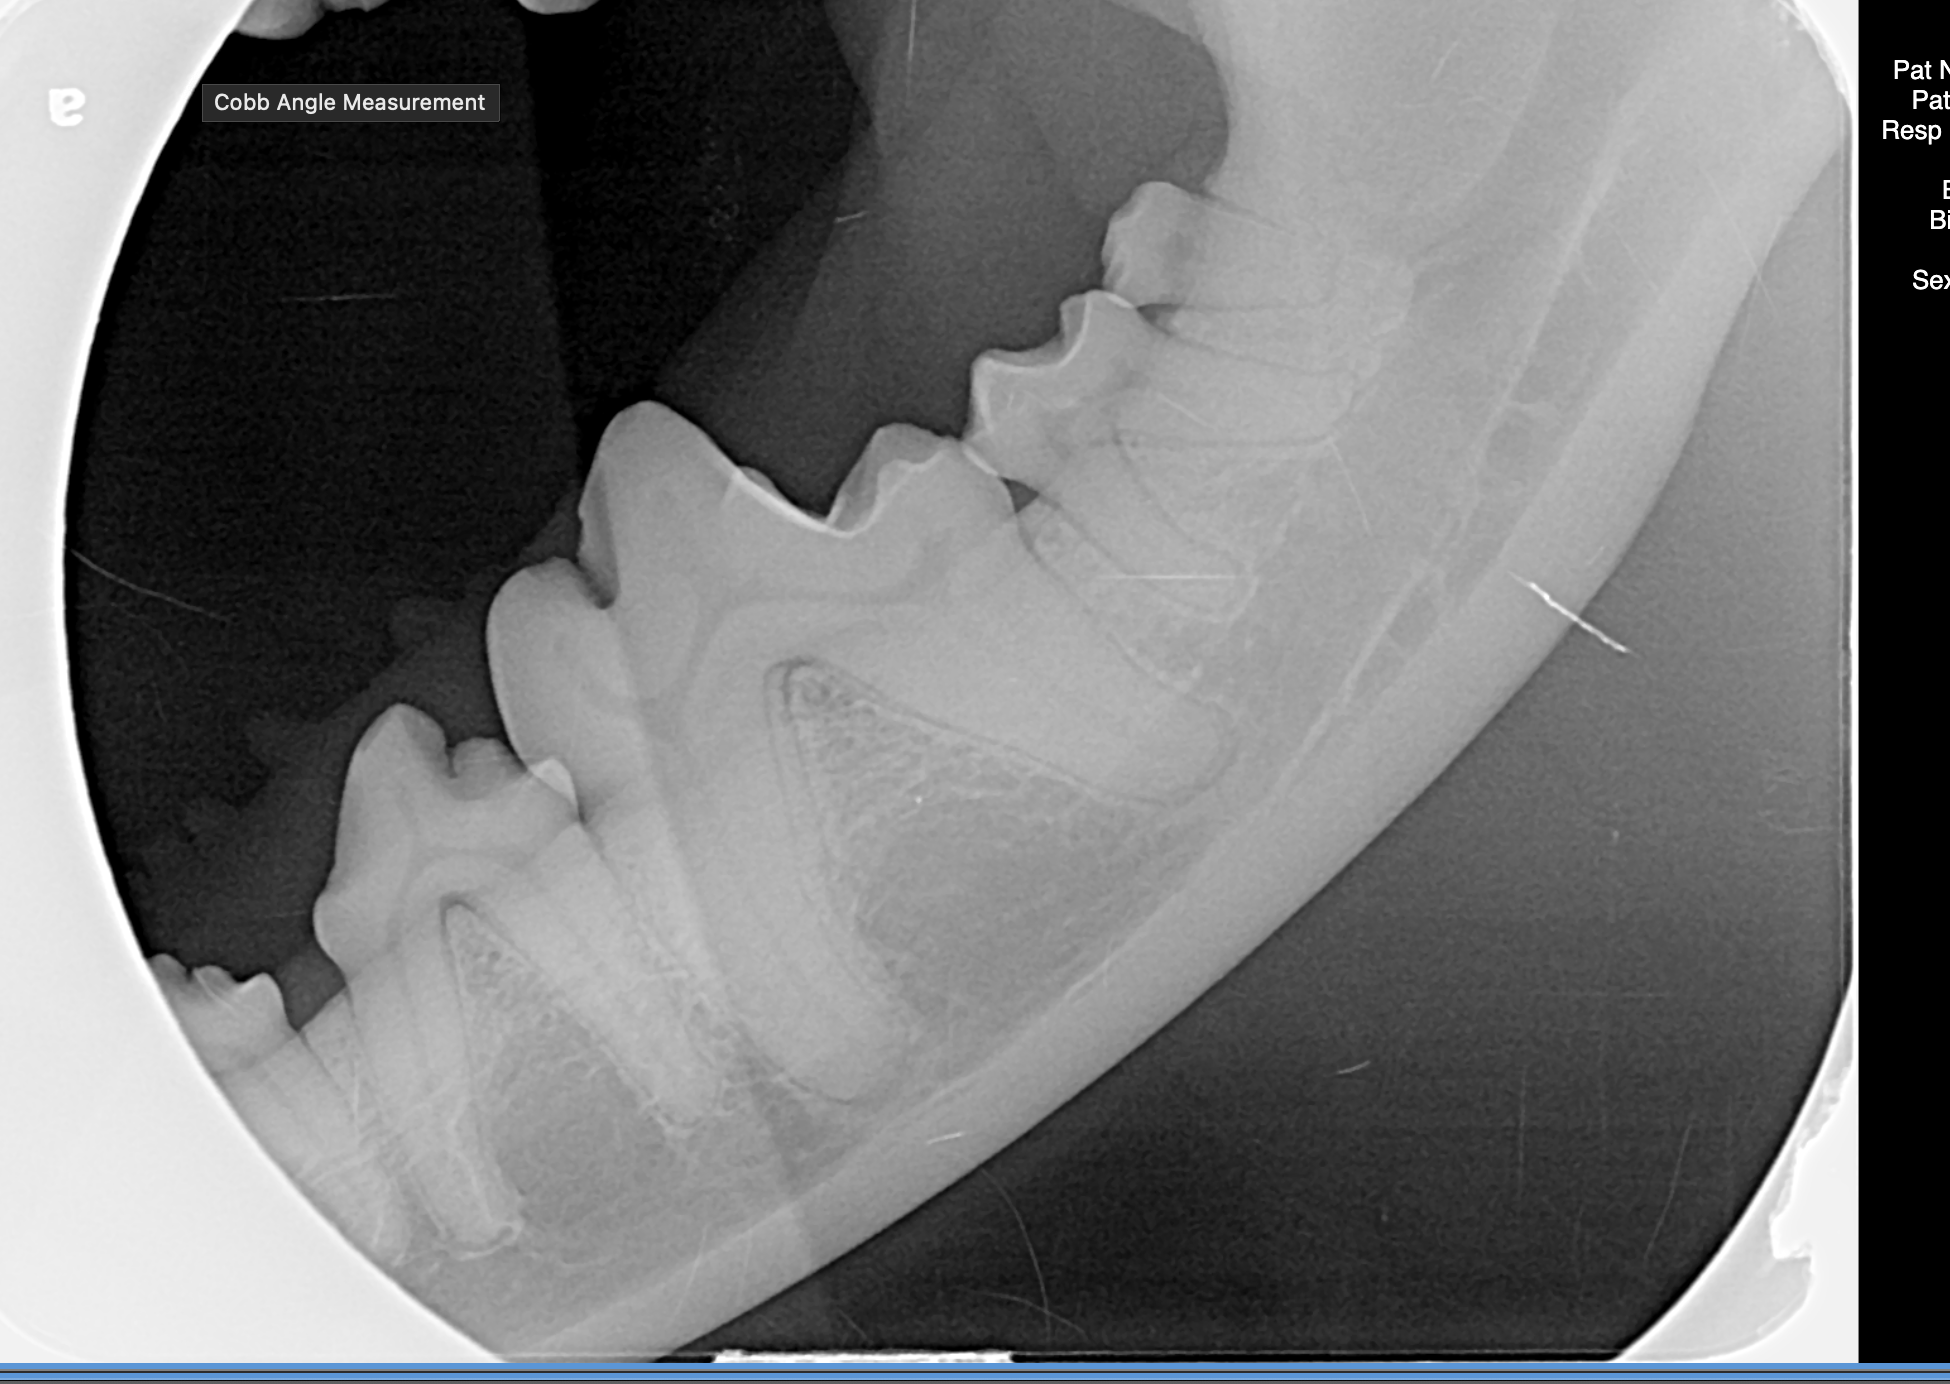

Dental issues are incredibly common in pets and a tailored, patient specific approach is key to getting the best outcome in every situation. No two families are alike, no two pets are alike and no two situations are alike - this is why we treat every case as an individual and aim to provide optimal care for every pet and family we serve.